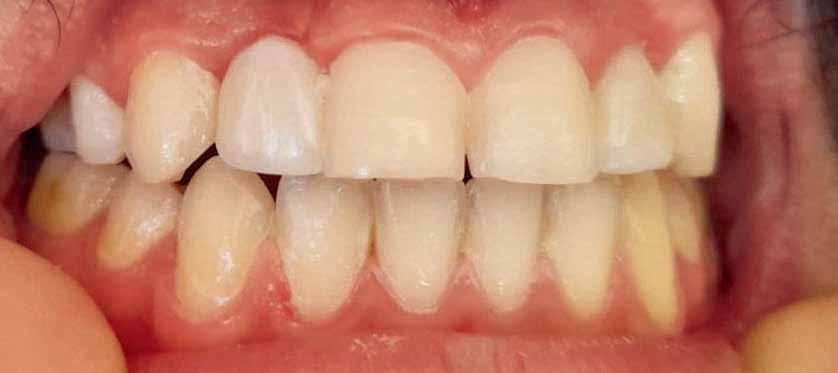

Exocad was used to design the restoration (fig. 13) and was milled from a super translucent multilayered zirconia (KATANA Zirconia STML; Kuraray Noritake). The milled restoration was cemented on the Ti-base with a resin cement (RelyX Unicem; 3M ESPE). Then, the definitive restoration was connected to the implant, and the Ti-base screw was tightened to 20 Ncm according to the manufacturer’s instructions. The screw access channel was sealed with sterilized PTFE and photopolymerized composite resin (Filtek Supreme Ultra; 3M ESPE). The definitive restoration was evaluated for centric and eccentric occlusal contacts and then finished and polished (fig 14,15).

tissue during the healing period in one-step recording direct from the source and ensured this measurement protocol is more accurate than the conventional step which cumulates routine error in the impression taking with weight material, the poured stone model and hand-manual measuring. The use of CAD/CAM technology in implant crown design has the potential to improve the accuracy and e ciency of the restoration process, providing patients with a functional and aesthetic solution to their dental needs24 Healthy peri-implant gingiva is important to ensure a good emergence profile, particularly in the esthetic zone. It plays a role in preventing periimplant disease by forming a barrier to e ciently protect underlying bone and prevent access to microorganisms. In addition, after the final restoration, time may be required for soft tissue to fill the embrasure, which is more predictable with healthy tissue, shows adequate interdental papilla, well contoured gingiva, and the presence of stippling and no inflammation, indicative of healthy peri-implant tissue25

The use of customized healing abutments seemed to be an appropriate solution to support and maintain the soft and hard tissue contours after immediate implant placement in both the anterior regions. This reinforces the importance of longterm monitoring and care in the management of dental implants, emphasizing that immediate placement strategy can achieve comparable outcomes in terms of bone health and implant stability using customized healing abutment, provided that appropriate post-operative care and follow-up protocols.